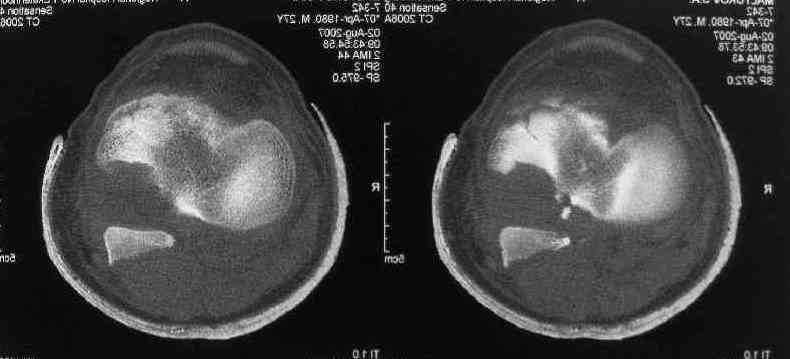

Для определения доступа сагитальные срезы менее информативны, необходимо иметь корональные срезы.

Корональные срезы дают информацию об апексе перелома, и также информацию о вовлечения суставной поверхности, что является немаловажным для прогноза.

Операция из разряда травматологической "экзотики" прошла успешно. Доступ понравился:анатомичный, хорошая визуализация, удобно работать и оператору и ассистентам. Наложили пневможгут, но воспользовались им только на этапе ревизии сустава. Фрагмент развернулся на 90 град. на 2-ух "жгутах": медиально - сухожилие m.semitendinosus, латерально - задняя крестообразная связка. Мобилизовали,развернули и уложили на место без особого труда. Фиксировали отмоделированной 1/3-трубчатой пластиной. Мениск оказался неповрежден. Сустав стабилен. Обошлись без

иммобилизации, планируем начать ранние движения. Остальное на фото, дополнительно приложены корональные срезы КТ.